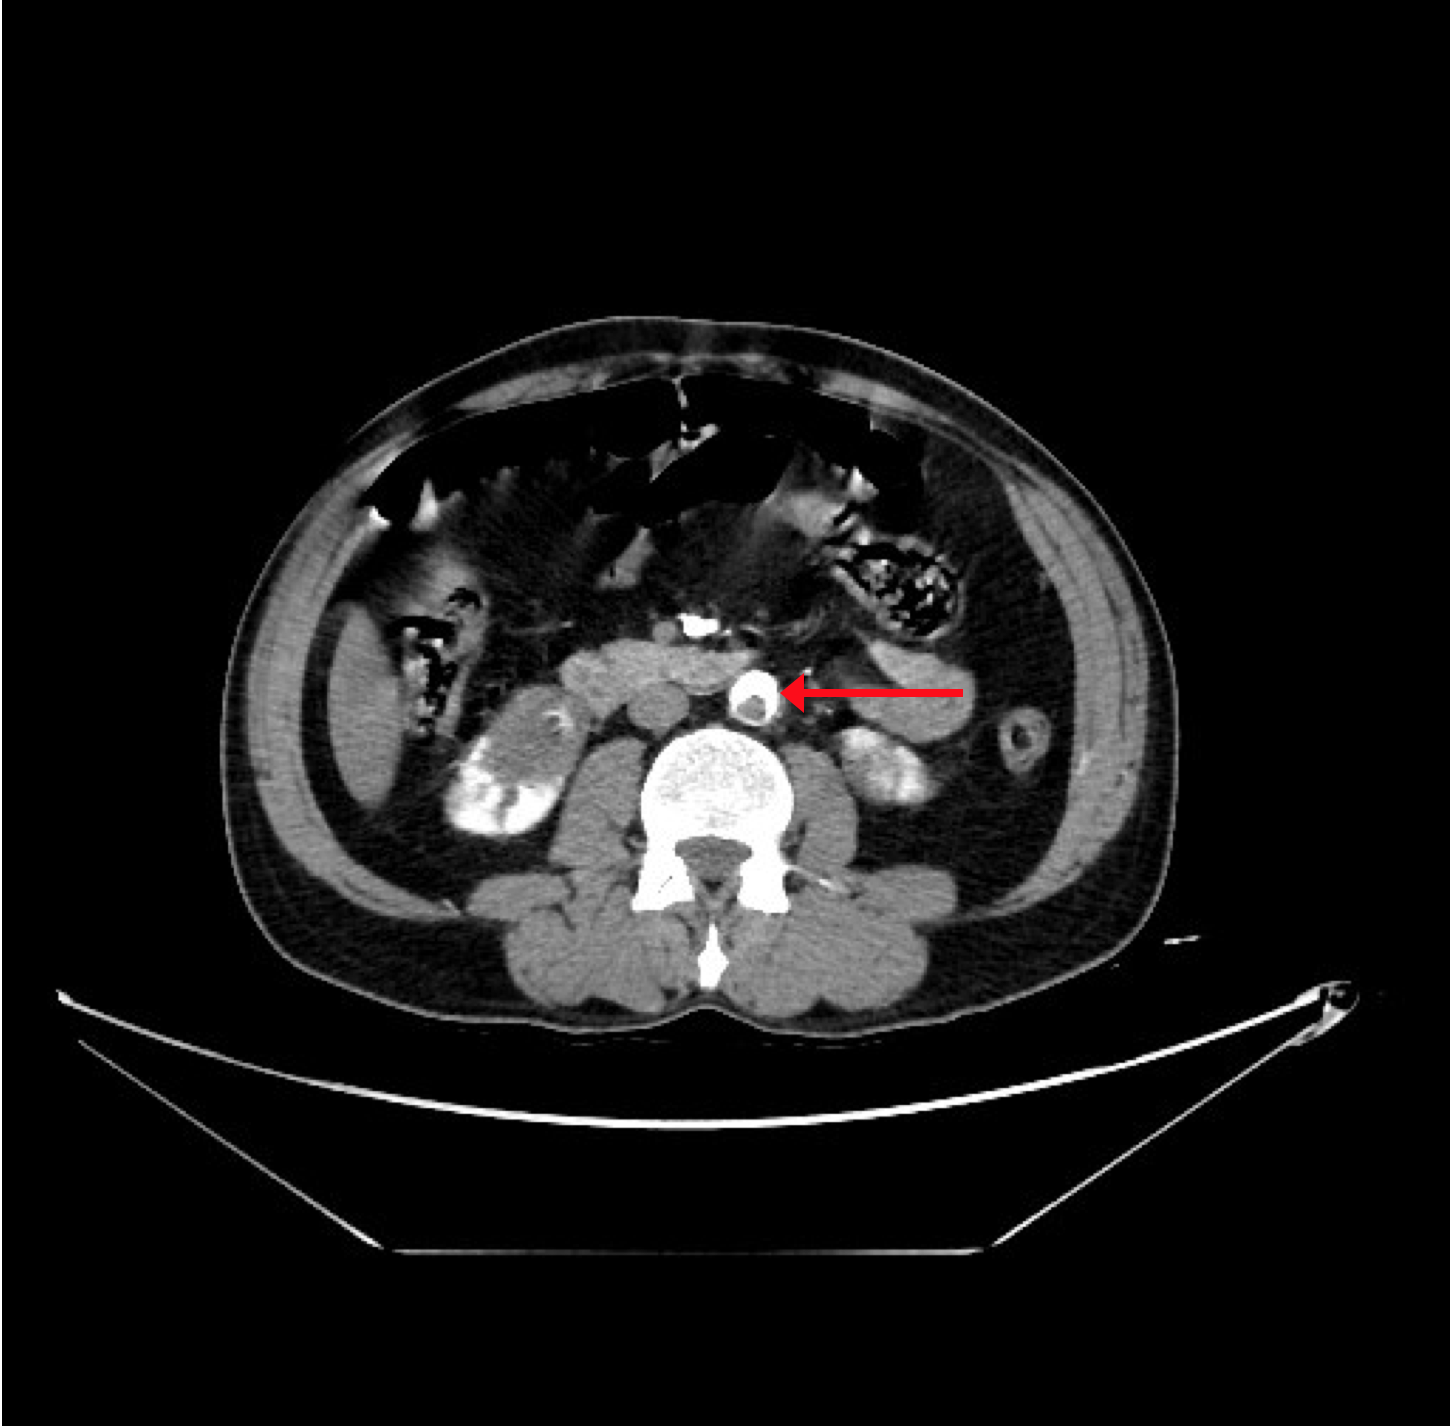

The CT angiogram and CT chest aortogram revealed a hypodense filling defect in the aorta below the level of the renal arteries causing partial occlusion of the aorta (Figure 2). There was complete occlusion of the left common iliac artery just after bifurcation of aorta extending up to the common femoral artery (Figure 3). There was good contrast uptake in right common iliac artery, femoral artery, superficial femoral artery up to the popliteal artery then the abrupt cut off of right popliteal artery present with no contrast filling seen in the distal arteries (Figure 4 and 5). Additionally, multiple bilateral wedge shaped infarcts seen in both the kidneys and the spleen (Figures 6). Chest x-ray was normal.

Figure 2: CT aortogram revealing filling defect in the infra-renal aorta.